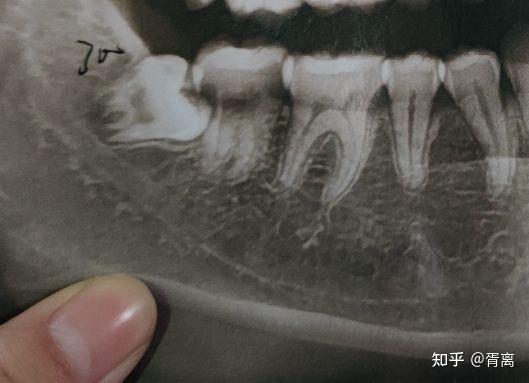

牙齿侧面x光,牙齿x光片侧面

附上我的牙齿部分x光照片

有人能教教我怎么看牙齿的x光片吗?